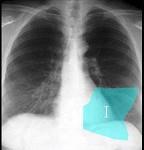

问题 如图所示正常胸部X线影像图像上,该英文字母所代表的肺段为 ( )

选项 A.内基底段 B.前基底段 C.外基底段 D.后基底段 E.背段

答案 D